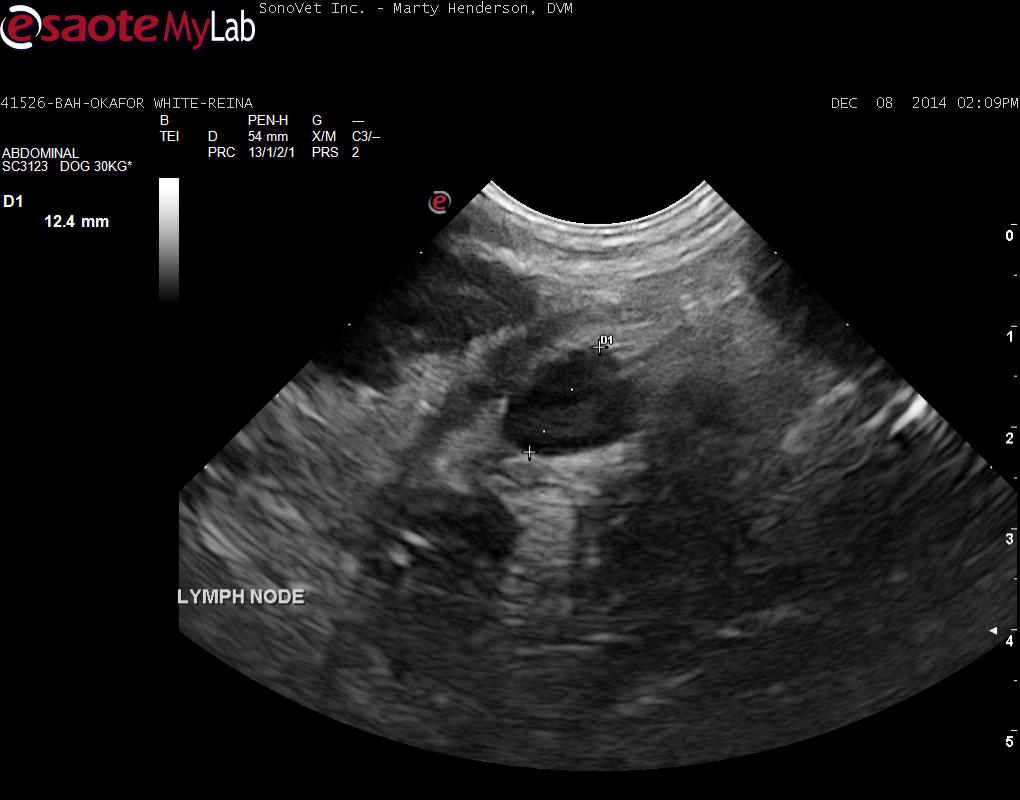

A 6-year-old female Labrador was presented for evaluation of loose stools and weight loss. Abnormalities on serum biochemistry were elevated liver enzyme activity and hypoalbuminemia. On survey thoracic radiographs, a mild interstitial pulmonary pattern was evident.